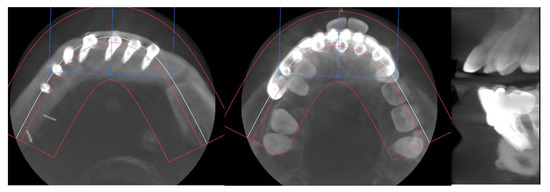

Simultaneously, a cortico-cancellous graft of the left anterosuperior iliac crest was obtained. The graft was fixed to the fibula using the CAD/CAM titanium mesh and 1.5 mm screws (Figure 5B). There was no intraoral exposure of the graft and an increase in the vertical dimension of the fibula was achieved and demonstrated by panoramic radiograph and CT scan (Figure 6A,B and Figure 7A,B).

CT Scan and CBCT were performed in the postoperative follow-up, and bone volume and bone resorption (Figure 13 and Figure 14) were evaluated by the Radiology Department of the hospital. A morphing reconstruction was performed to compare the lower facial third showing an improvement in the aesthetic profile and facial projection (Figure 15).

Figure 7. Postoperative CT scan. (A) Axial CT Scan demonstrating the stability of the transverse dimension of the fibula with respect to the remnant mandible. (B) The three-dimensional preservation of the iliac crest graft with CAD/CAM mesh makes it possible to double the height of the fibula.

Figure 13. CT Scan and CBCT were performed in the postoperative follow-up, providing relevant quantitative data regarding bone volume and bone resorption.

Figure 14. CBCT performed in the follow-up to evaluate bone resorption before and after implant loading.